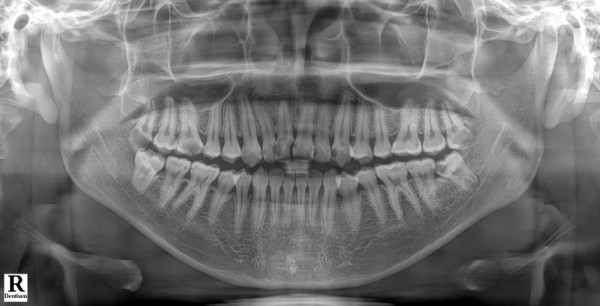

상하악 모든 사랑니 발치,

심하게 손상된 앞니는 발치 후 임플란트로 대체,

그리고 신경 치료가 필요한 여러 치아들에 대해서는

지르코니아 크라운으로 수복하기로 계획했습니다.

총 6개월에 걸쳐 여러 차례 수면 진정 하에 단계적으로 치료를 진행했습니다.

사랑니 발치부터 시작해서 신경 치료, 임플란트 식립,

그리고 마지막 보철물 장착까지 모든 과정을 차근차근 완료할 수 있었습니다.